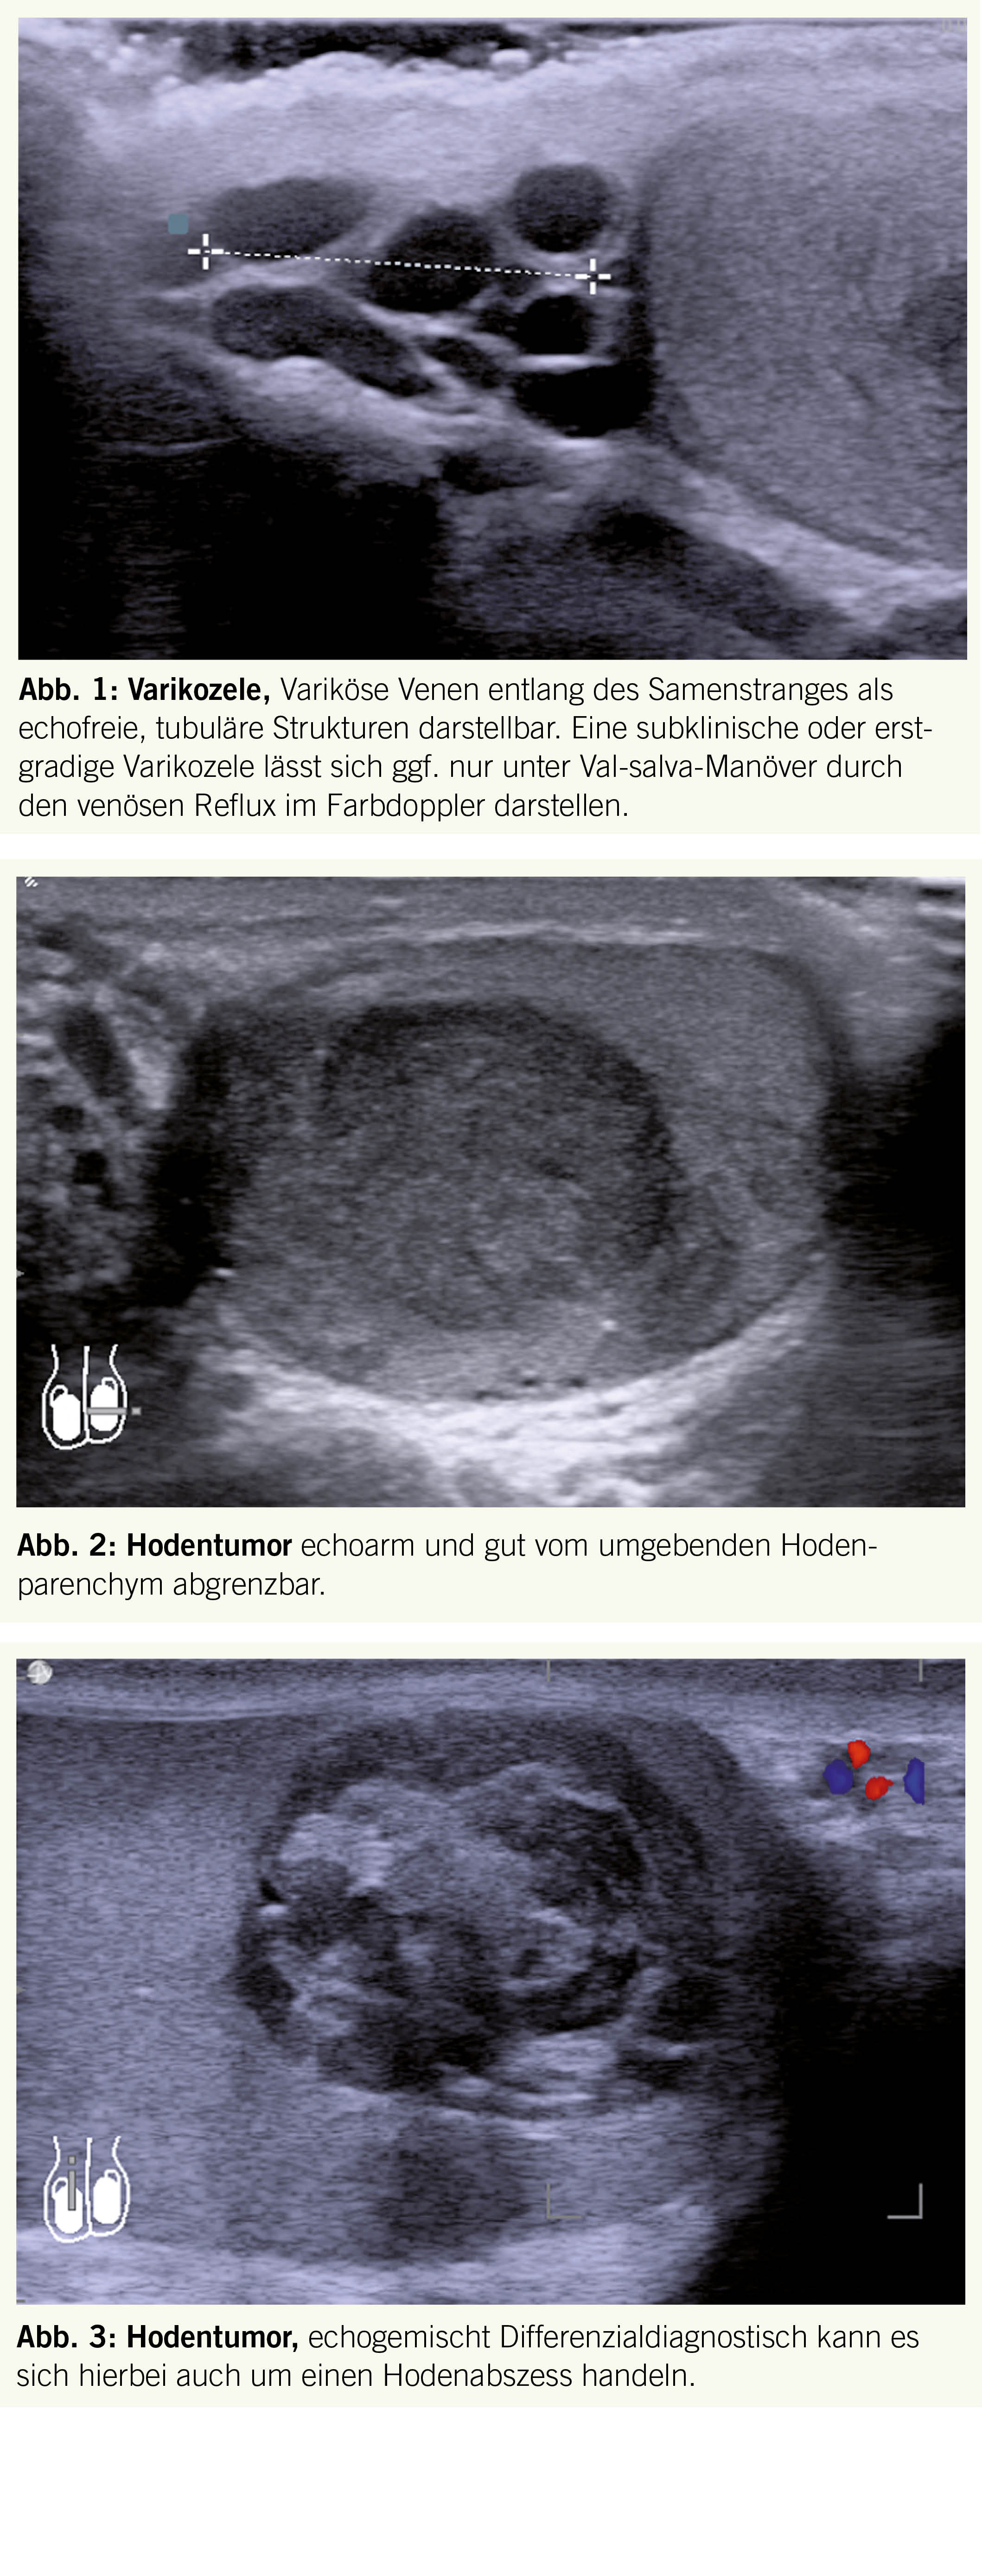

Diagnostisch sollte eine sonographische Untersuchung des Skrotums erfolgen wobei sich die varikösen Venen entlang des Samenstranges als echofreie, tubuläre Strukturen darstellen lassen (Abb. 1).

Durch den Farbdoppler lässt sich der venöse Reflux unter Valsalva-Manöver gut darstellen.

Die anschliessend klinische Untersuchung beinhaltet die Palpation des betroffenen und des kontralateralen Hodens, der Brustdrüsen sowie der inguinalen, axillären und supraklavikulären Lymphknotenstationen. Die Sonographie des Hodens, wo Tumore meist als hyperperfundierte, echoarme bis echogemischte irreguläre Läsion im Hodenparenchym imponieren, ist das primäre Diagnostikmittel der Wahl (Abb. 2 und 3).